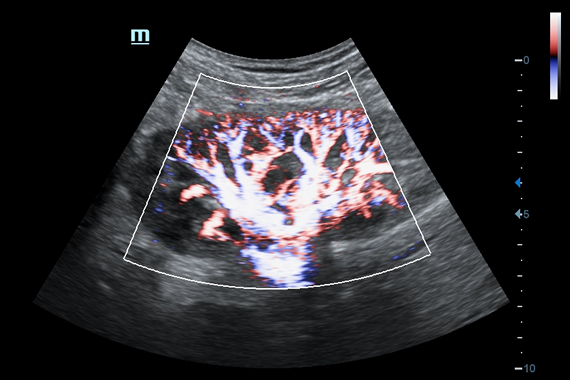

• HR Flow - режим отображения кровотока с высоким временным и пространственным разрешением для точной и однородной визуализации сосудов, в том числе самых мелких.

Цветовой допплер:

Да

• HR Flow - режим отображения кровотока с высоким временным и пространственным разрешением для точной и однородной визуализации сосудов, в том числе самых мелких

• Vascular package - предустановленные параметры, аннотации, маркеры, программы измерений для ангиологии, включая транскраниальные исследования